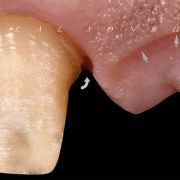

TV Show presenter visited my clinic complaining of unpleasant bridge that had been placed couple of years ago. Thorough clinical and radiographic examination was done including smile, teeth and gingival analysis. Implant as a treatment option was excluded due to patient preference. Let us see how I dealt with this case!